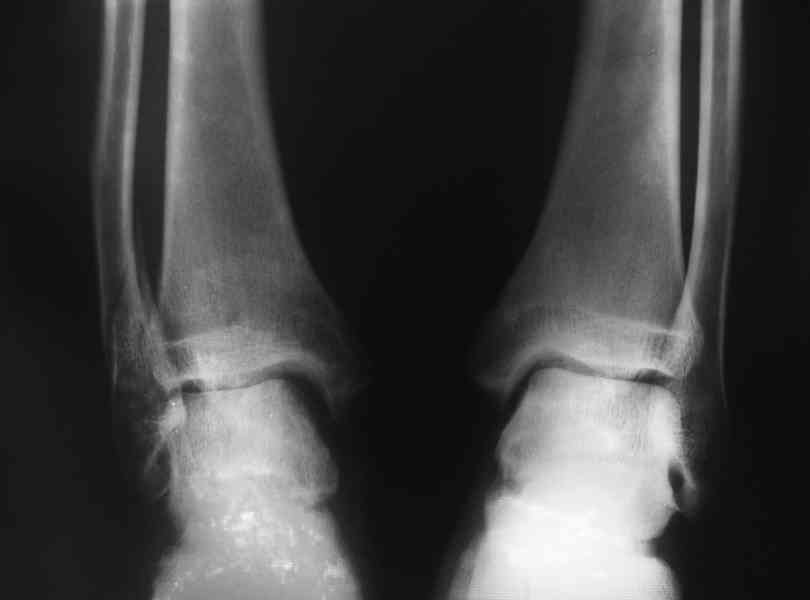

перелом малой берцовой с разрывом синдесмоза

У меня был открытый перелом малой берцовой кости с разрывом синдесмоза и вывихом стопы кзади и кнаружи. Операции небыло. Месяц на вытяжке, два месяца в гипсе. Спустя еще два месяца начались боли в суставе при ходьбе. Сделал повторный ренген - незначительно разошелся синдесмоз и укоротилась малая берцовая кость. Предлагают два способа лечения:- Поставить болт-стяжку на синдесмоз.- рассечь малую берцовую кость и поставить аппарат Елизарова. Посоветуйте что делать?

Неободима болт- стяжка с диафизарной накладкой с целью восстановления взаимоотношения в г/стопном суставе